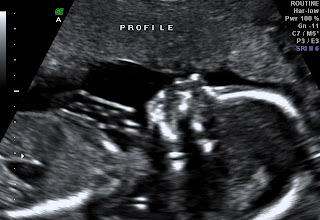

Well, the good luck had to wear off at some point. If any of you are still even checking this blog, let me explain why I haven’t been posting. First of all the babies are doing great. Wednesday we will find out their sexes. At our last ultrasound, the sonographer said her guess would be two girls but not to buy anything yet. So, we are anxiously awaiting our next appointment in T minus 36 hours.